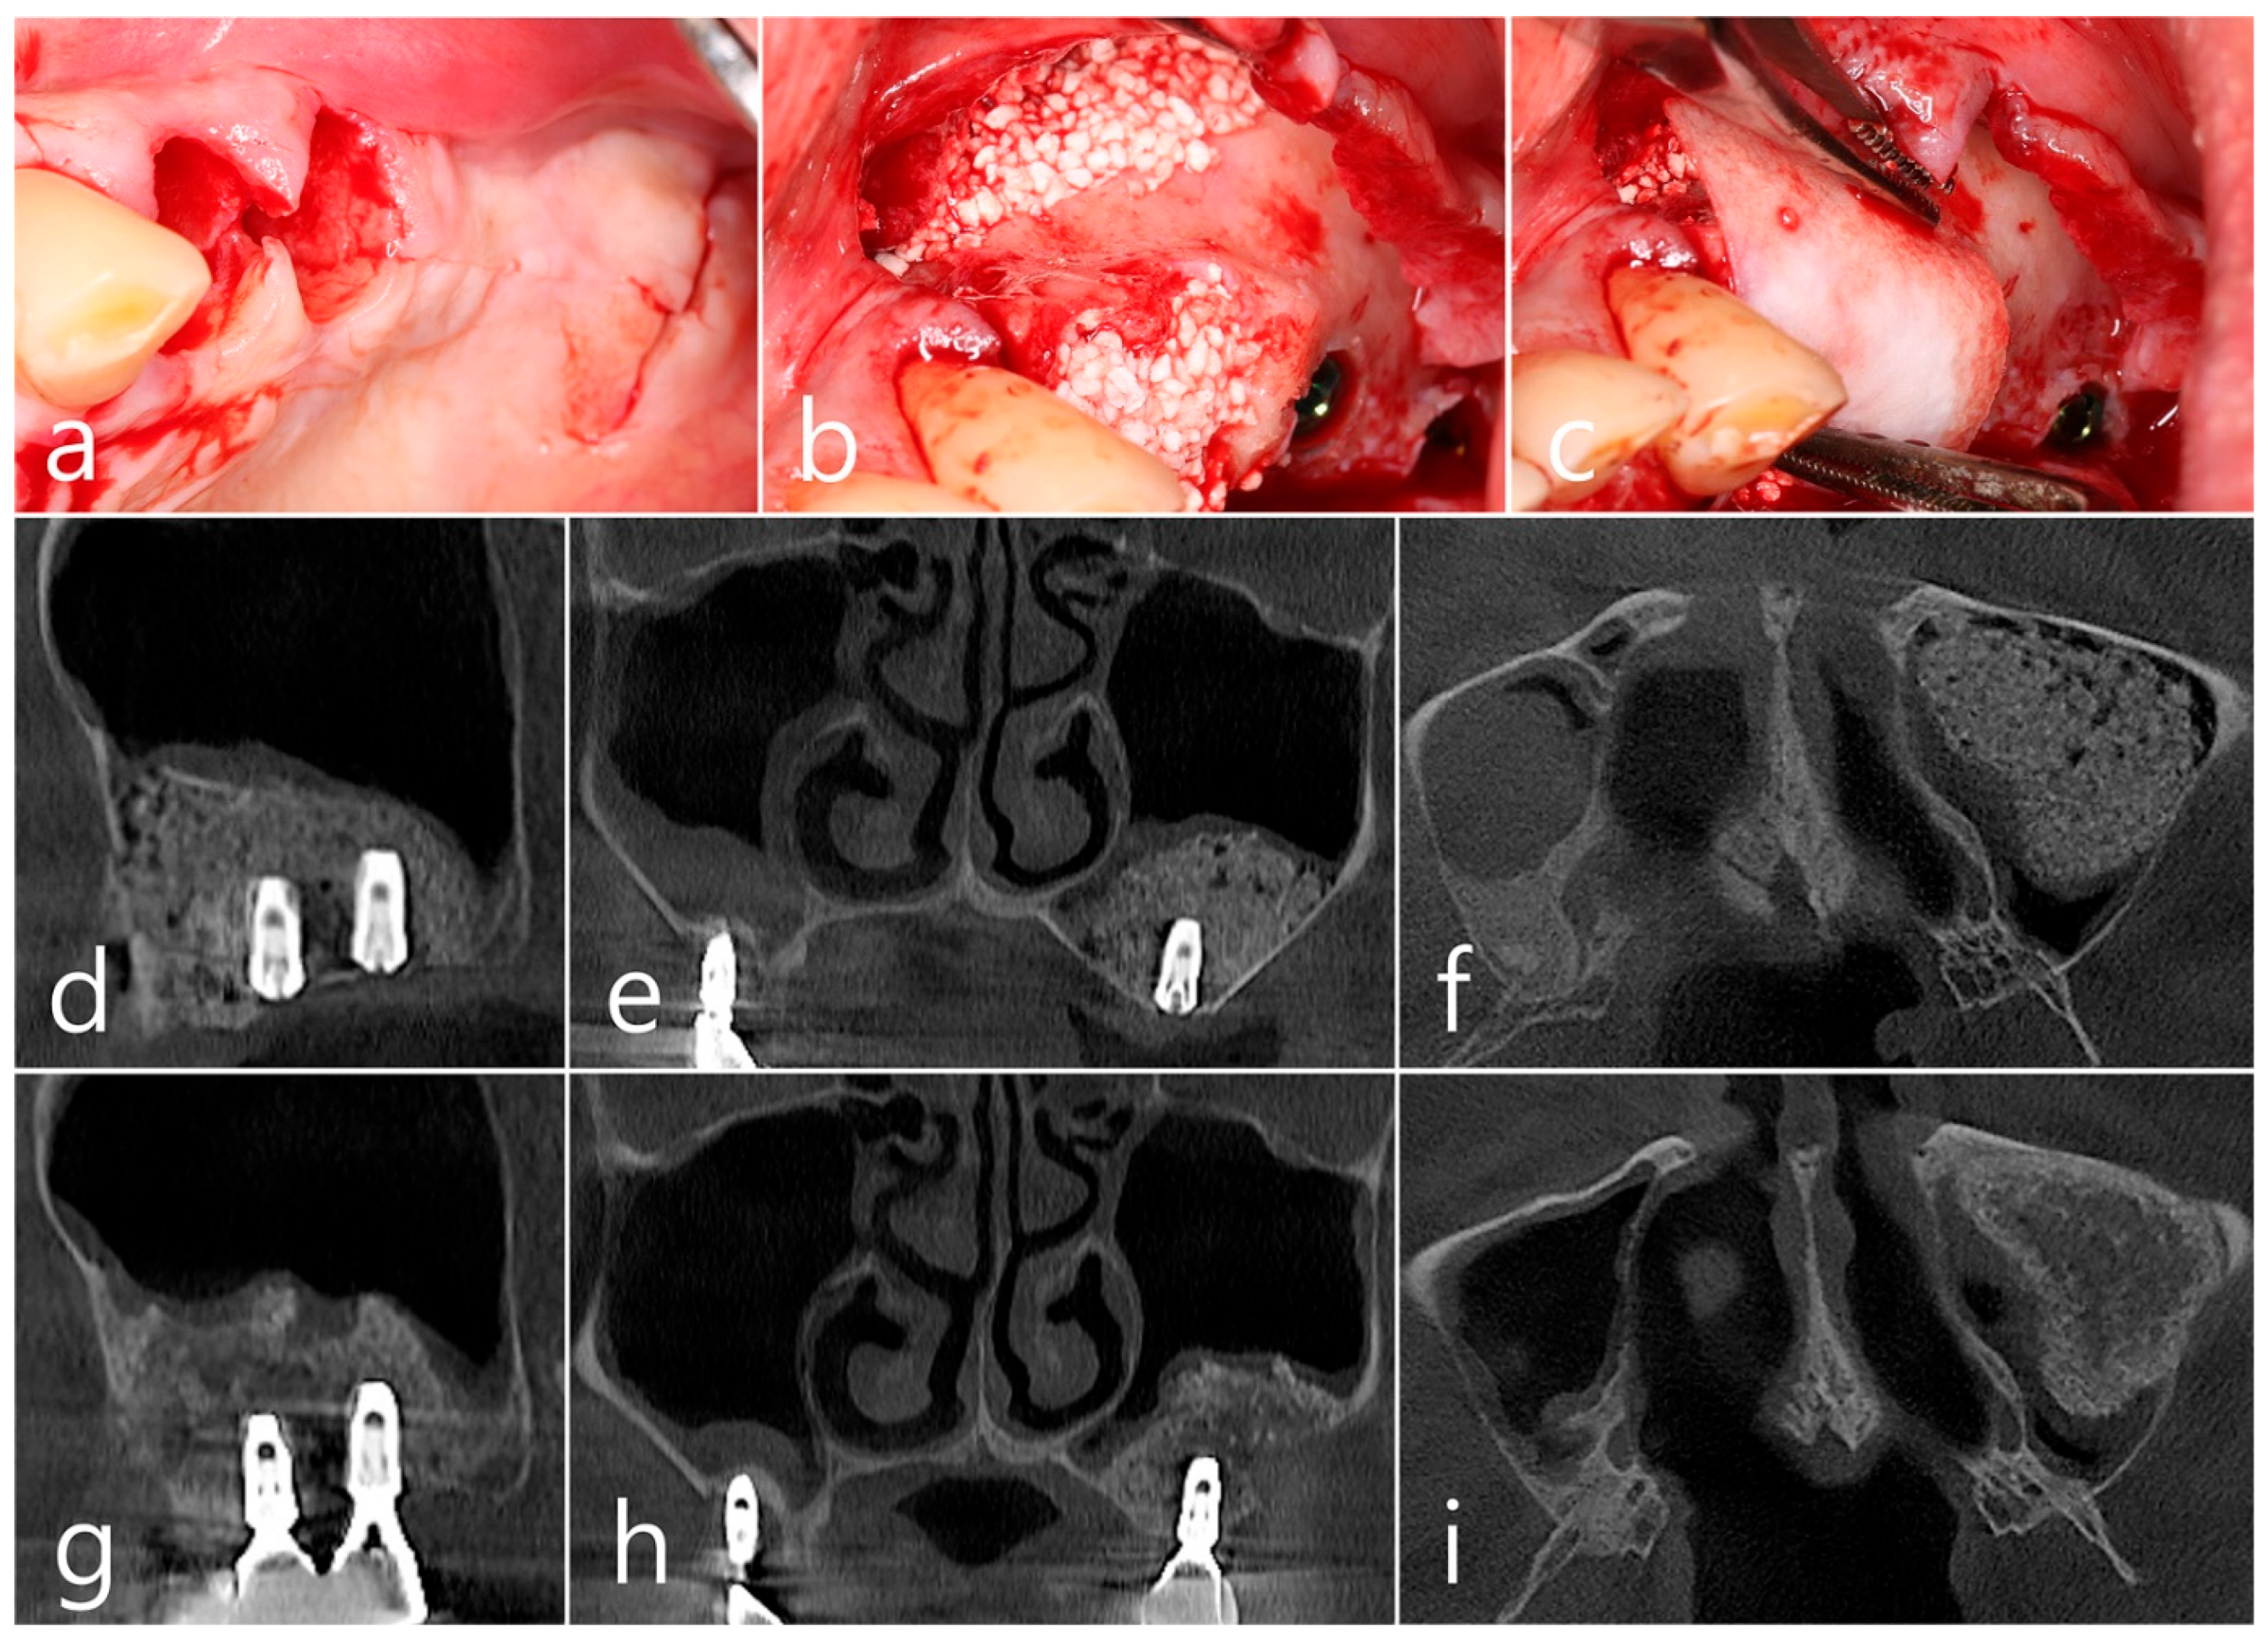

Surgical intervention was decided after the prosthesis was retrieved (Figure 9a). Under local anesthesia, the buccal mucoperiosteal flap was reflected. A severe bone defect was observed in the sinus bone graft of the #26 implant. Thorough debridement was performed on the bone defect in the maxillary sinus bone graft. There was no difficulty in removing the inflammatory granulation tissue because it bordered the surrounding healthy bone graft (Figure 9b). The exposed implant achieved osseointegration, but the large implant surface was exposed and contaminated. Mechanical decontamination was thoroughly performed using a titanium brush and titanium curette, and additional detoxification with tetracycline HCl was performed (Figure 9c). After sufficient saline irrigation again, a bone graft (Osteon II, Genoss, Suwon, Republic of Korea) was performed (Figure 9d). The bone graft area was covered with a resorbable collagen membrane (Genoss, Suwon, Republic of Korea) (Figure 9e). The mucoperiosteal flap was closed with 4-0 nylon. Healing was uneventful, and the prosthesis was re-inserted again 1 month after GBR. The specimen was fixed in 10% formalin for histopathological examination. In the specimen, granulation tissue infiltrated with inflammatory cells, and necrotic bone graft particles were observed (Figure 9f). The patient was followed up once every 6 months, and panoramic radiography and CBCT were taken 2 years after GBR (Figure 10a,b). The bony defect was filled with bone tissue, and no abnormal radiographic images were observed. Corticalization of the buccal bone was well achieved (Figure 10c,d).

Figure 9. (a) Surgical intervention was decided after the prosthesis was retrieved; (b) The buccal mucoperiosteal flap was reflected. Thorough debridement was performed on the bone defect in the maxillary sinus bone graft; (c) Mechanical decontamination was thoroughly performed using a titanium brush and a titanium curette, and additional detoxification with tetracycline HCl was performed after sufficient saline irrigation; (d) A bone graft was performed; (e) The bone graft area was covered with a resorbable collagen membrane. The mucoperiosteal flap was closed. Healing was uneventful; (f) In the specimen, granulation tissue infiltrated with inflammatory cells, and necrotic bone graft particles were observed (H-E stain).

Figure 10. (a,b) In panoramic radiography and CBCT images taken 2 years after GBR, the sinus graft site of the maxillary sinus was well filled with bone tissue, and no abnormal radiographic images were observed; (c,d) On coronal and axial images of CBCT, homogeneous findings were observed in the previous bone defect site. Corticalization of the facial bone plate was well achieved.